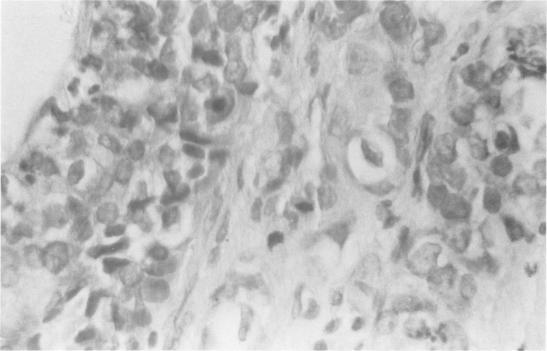

Carcinoma arising in the wall of a breast cyst during pregnancy.

A 23-year-old patient developed a carcinoma in the wall of a breast cyst during the second trimester of an otherwise uncomplicated pregnancy. A review of the literature revealed 7 reported cases of carcinoma of the breast arising in a cyst wall. However, none of these these cases has been associated with pregnancy. The relationship of fibrocystic disease and carcinoma of the breast is discussed. The possible influence of pregnancy and age on the prognosis of this patient are also considered.

一名23岁的患者在妊娠中期,于一个原本无并发症的乳腺囊肿壁上发生了癌变。文献回顾显示,有7例报道的乳腺癌发生于囊肿壁。然而,这些病例均与妊娠无关。文中讨论了纤维囊性疾病与乳腺癌的关系。还考虑了妊娠和年龄对该患者预后可能产生的影响。